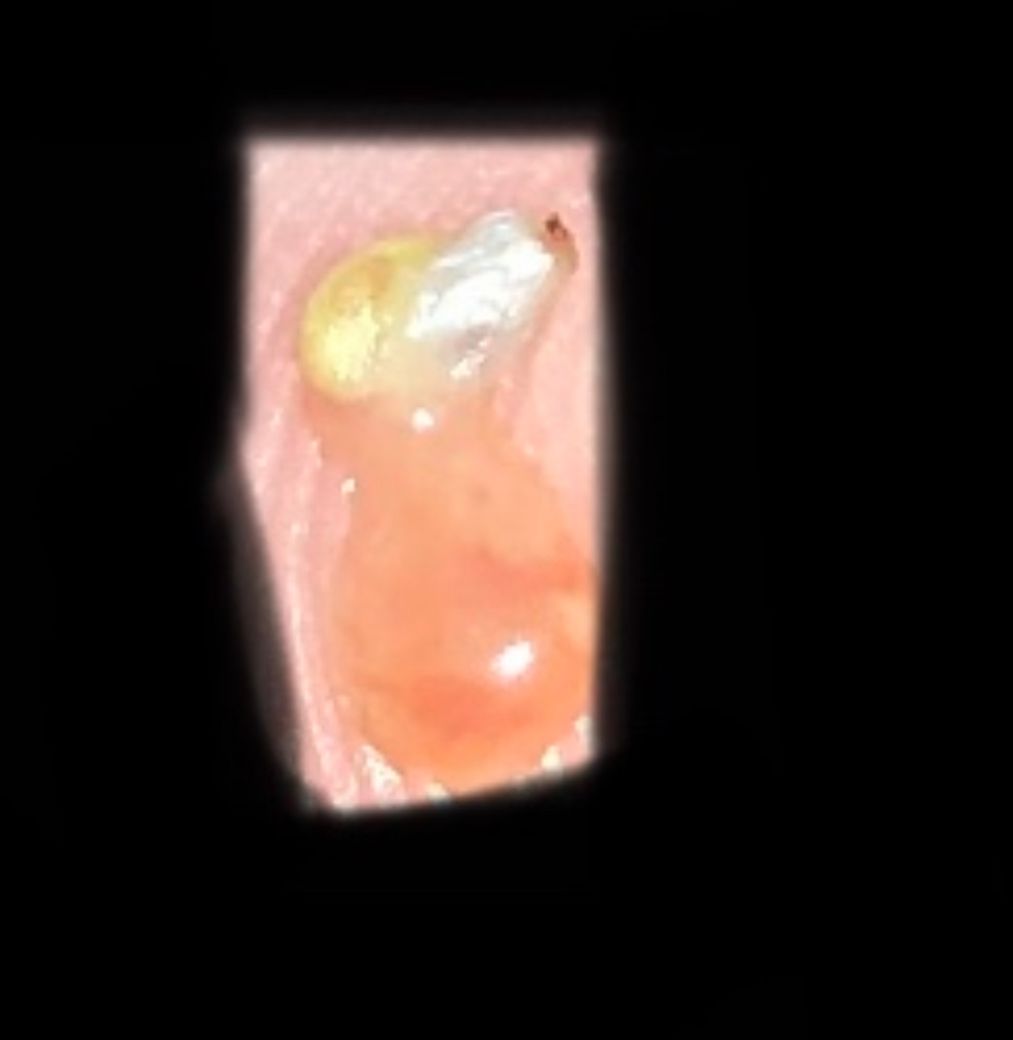

현재 상체쪽 상태입니다 전체적으로 이런 편이에요

그리고 짜보면 이런 피지 같은 게 나와요ㅠ

• 2번 째 사진